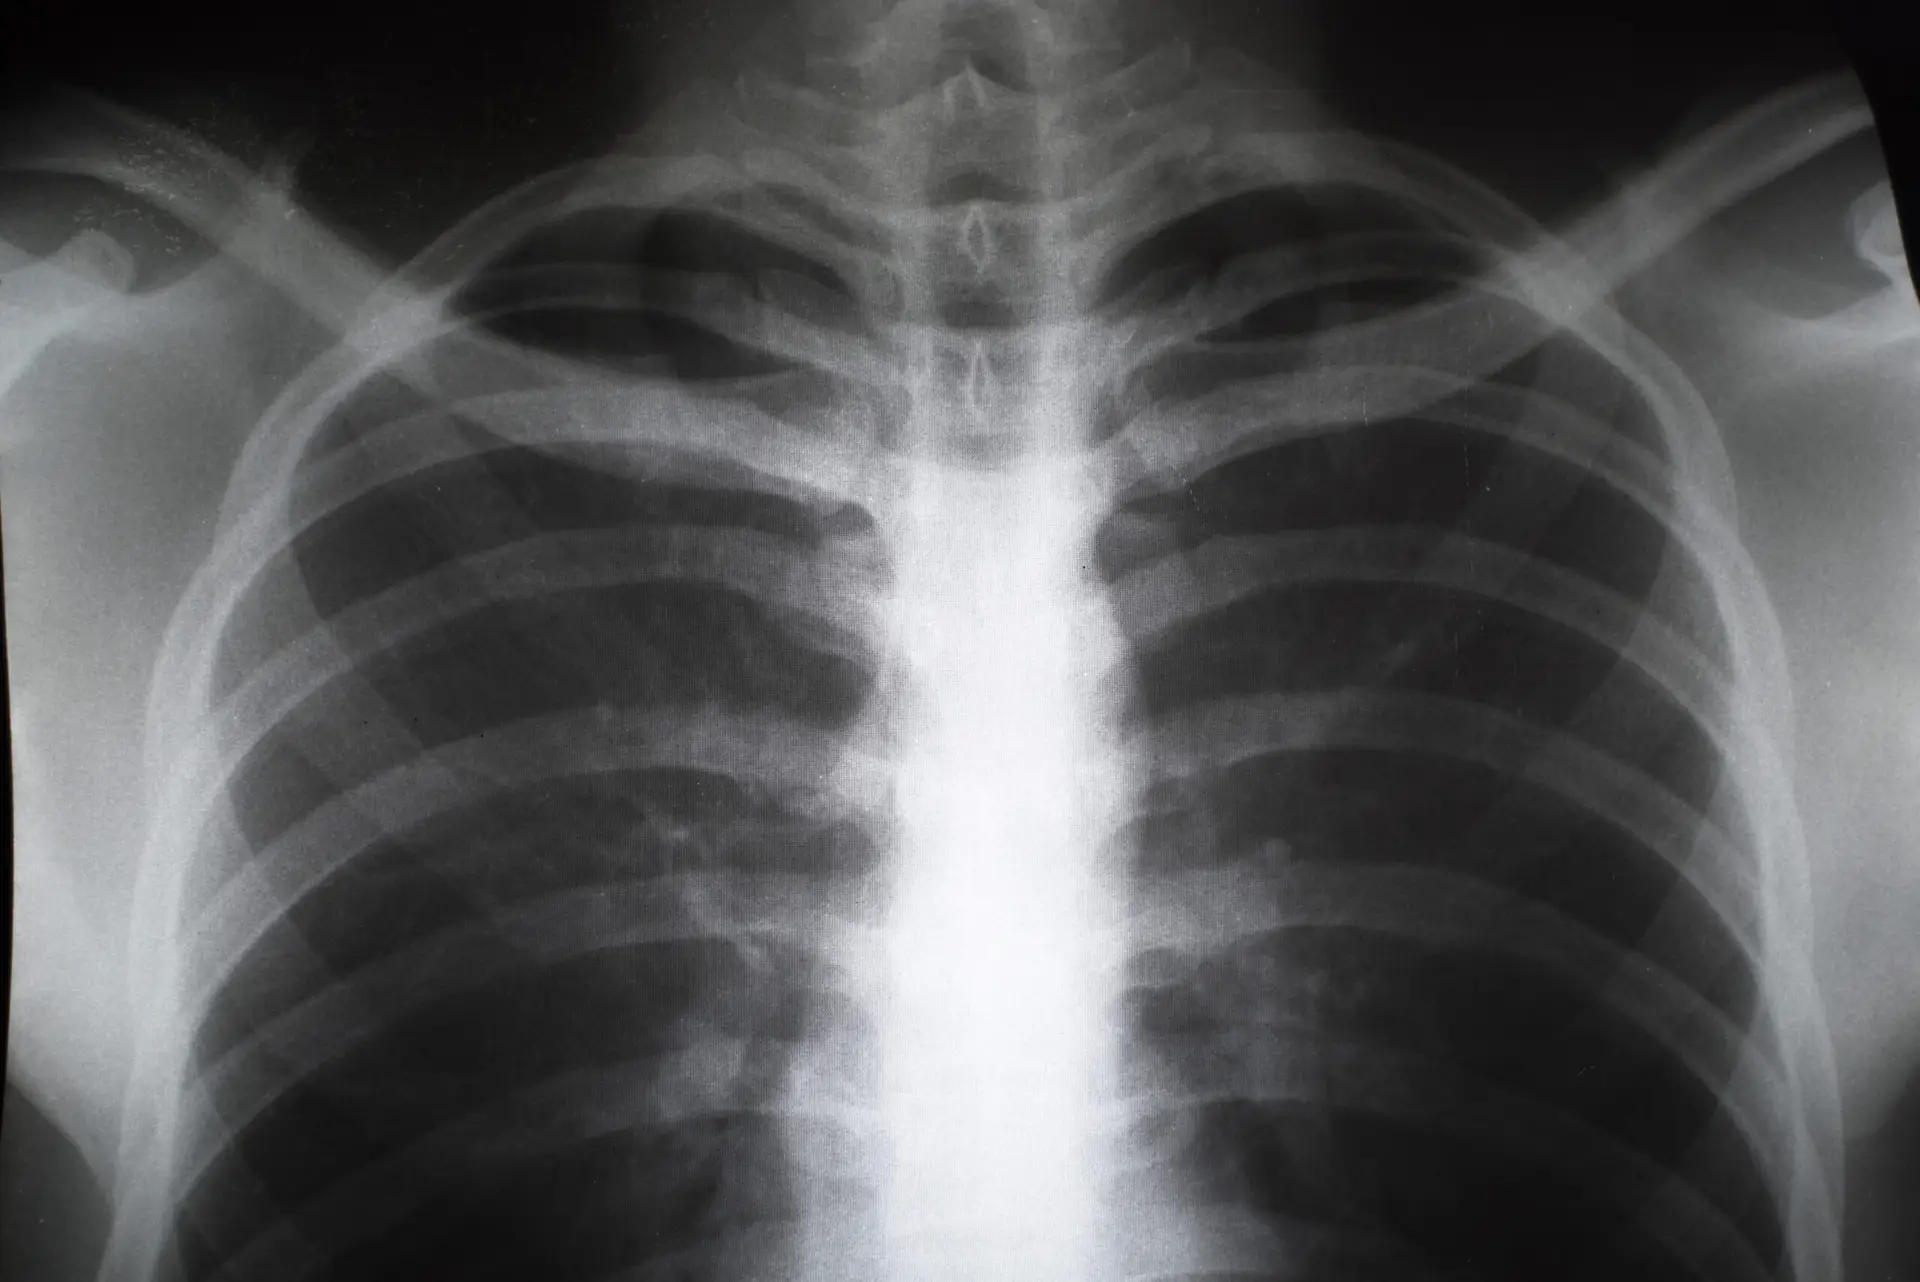

broken sternum x-ray

• X-rays: A lateral or anteroposterior chest X-ray is a standard way to diagnose a broken sternum and other chest injuries, including rib fractures, a broken collarbone injury, and pulmonary contusion.